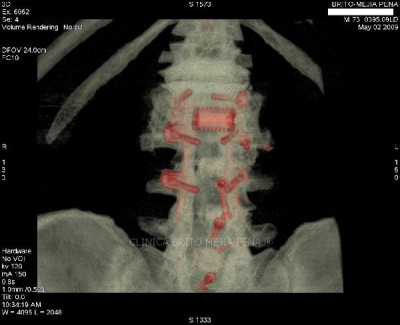

Instrumentalización columna 3D